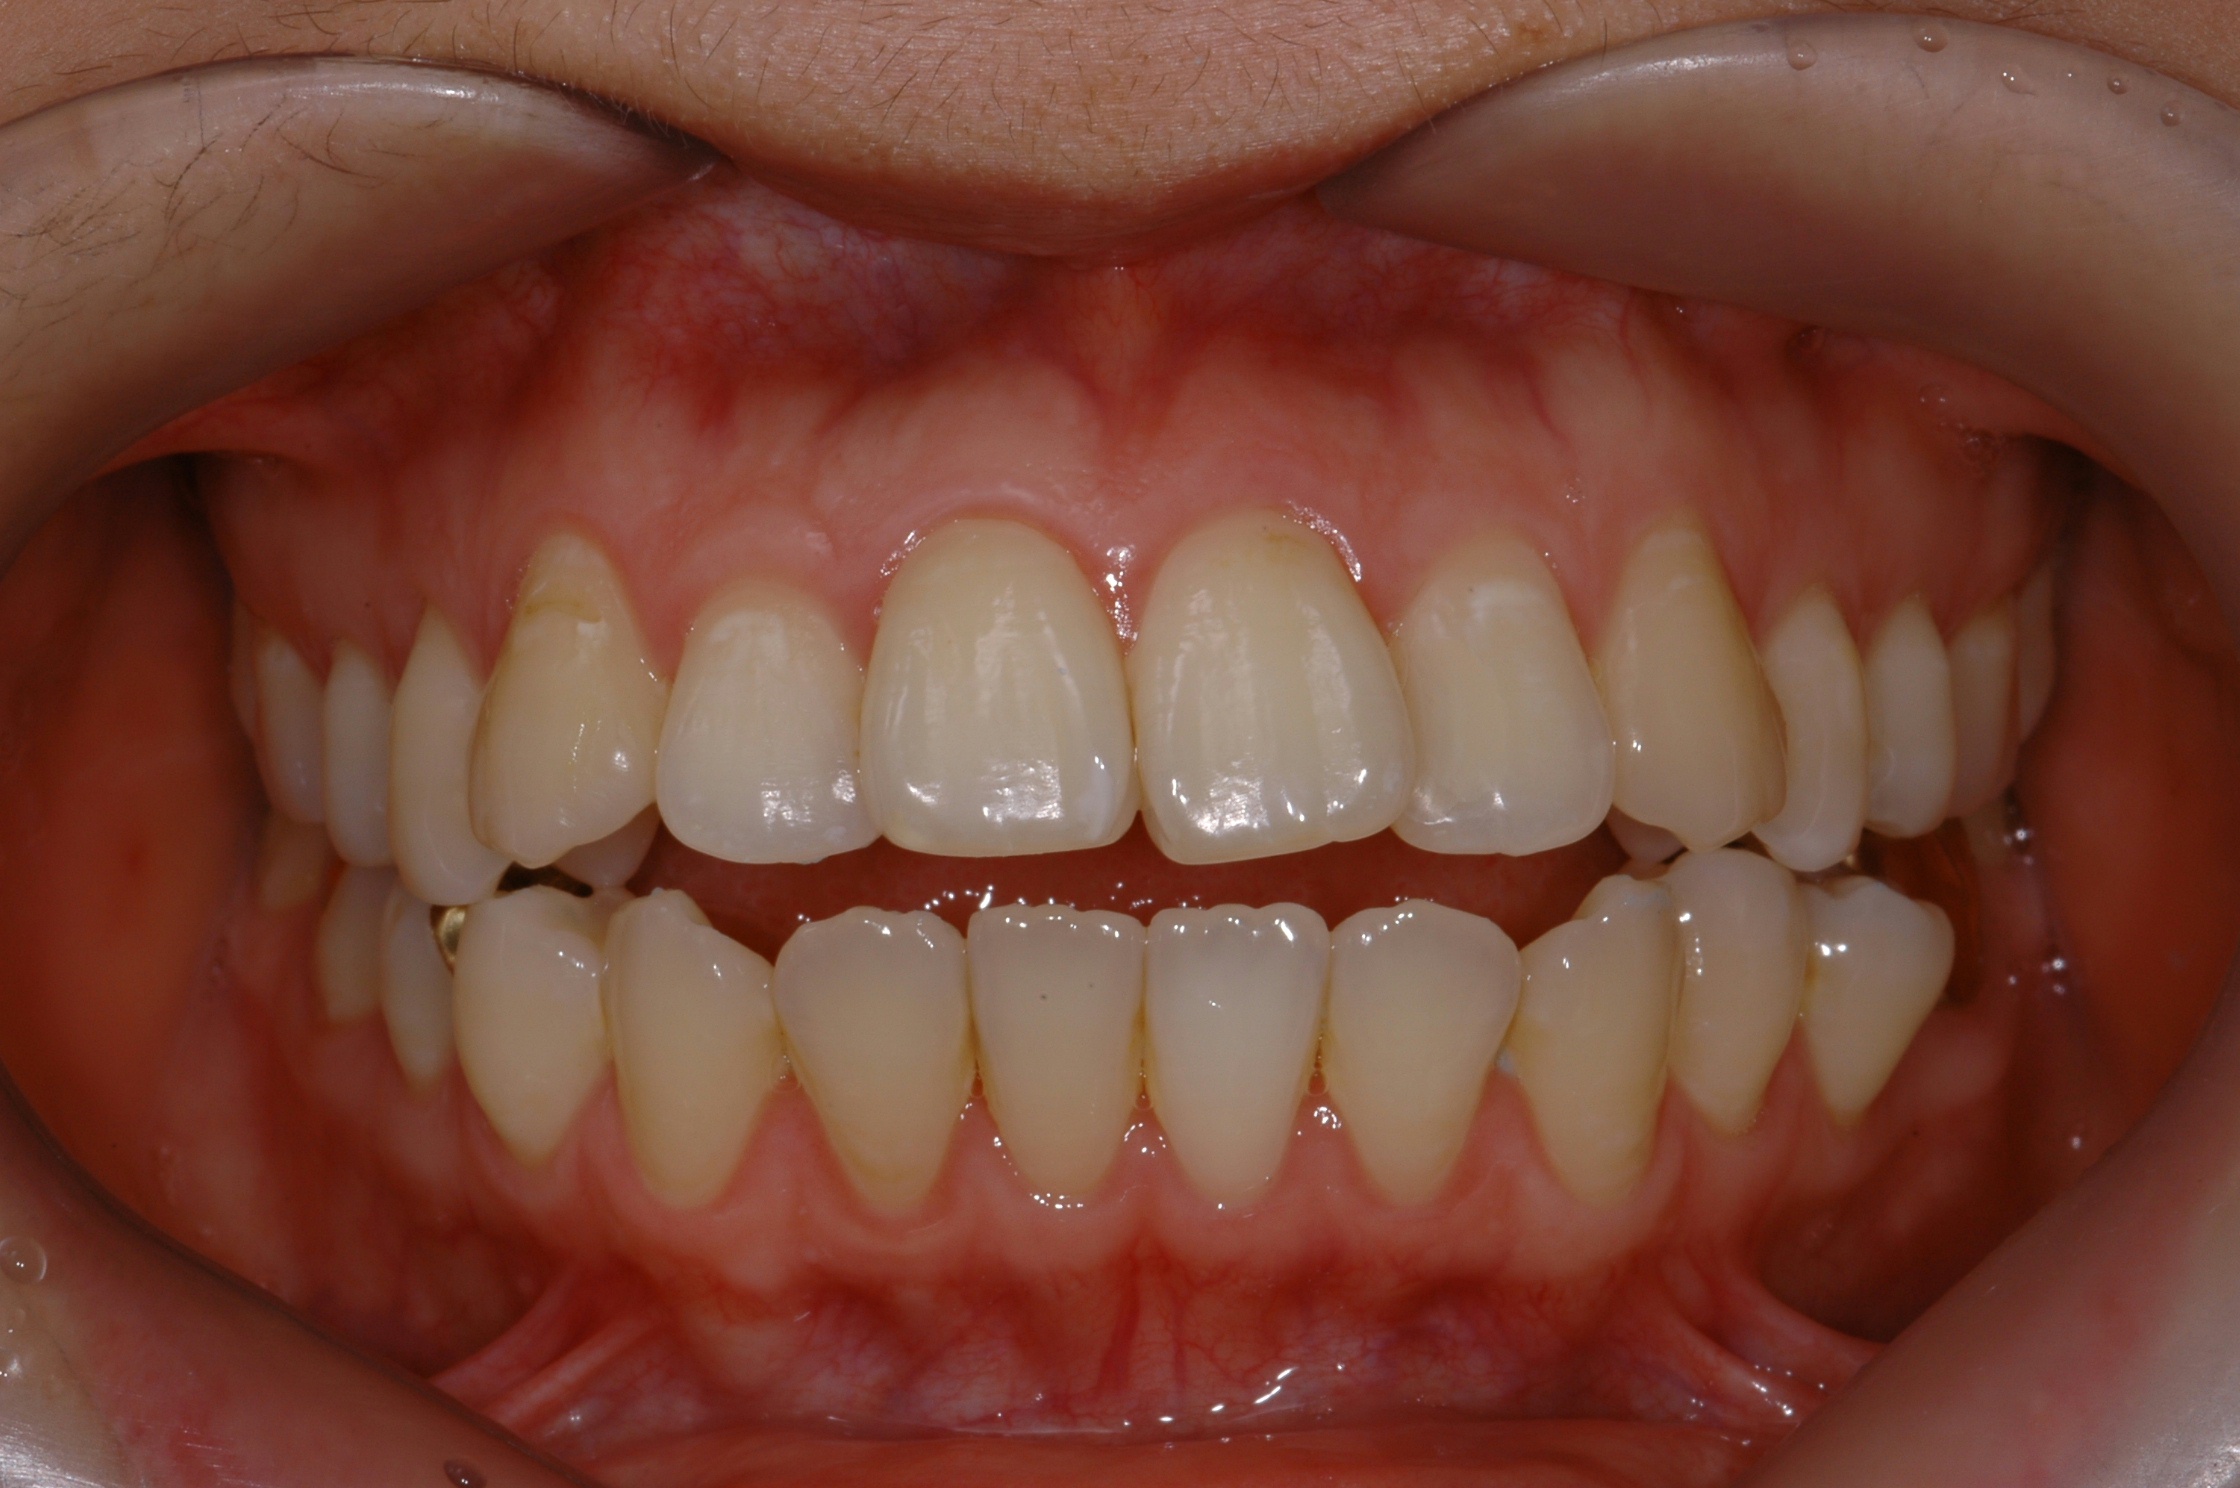

치료 전 사진입니다.